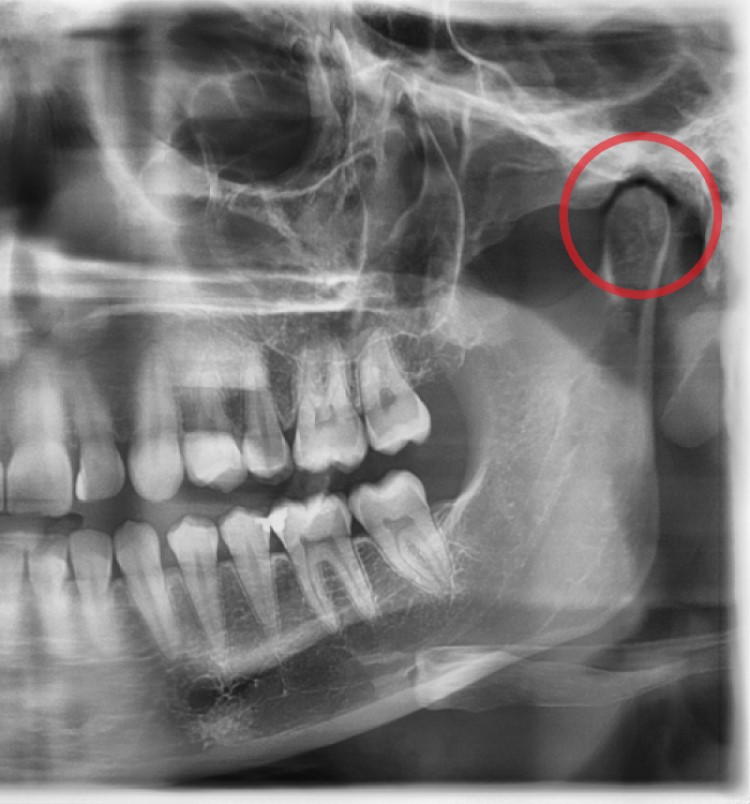

The temporomandibular joint (TMJ) is the name of the joint located on either side of your head, just in front of your ears. These joints connect your jawbone to skull. This joint in combination with other muscles and ligaments, lets you chew, swallow, speak and yawn. When you have a problem with the muscle, bone or other tissue in the area in and around the TMJ, you may have a TMD.

For patients with headaches or facial pain, our dentist does an examination and a series of tests to rule in or out your joints, teeth or facial muscles as a source of your distress. Testing for sleep apnea is often considered because of the high correlation with TMJ issues. For some patients, treatment can be done via orthodontic techniques such as Invisalign.